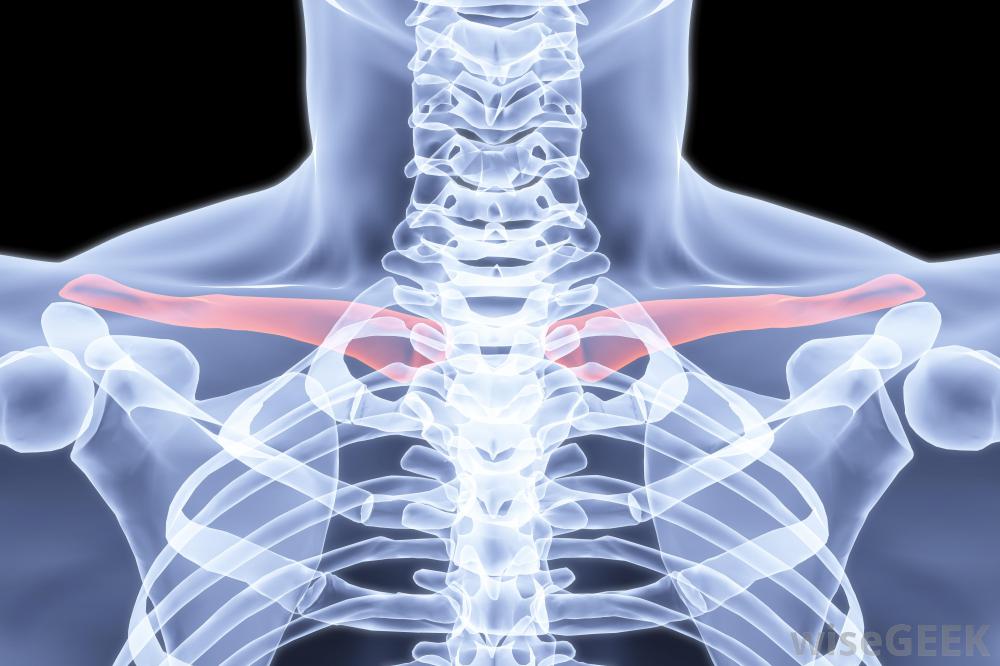

肩关节活动性降低、僵硬和肿胀是锁骨远端骨溶解。骨溶解是指骨中矿物质(如钙)的流失,导致骨头软化或溶解。在锁骨远端骨溶解中,末端或远端,锁骨开始缓慢分解和溶解。这可能是由AC关节的单一损伤、较小的重复性损伤、AC关节上的重复应力(如举重)或可能影响骨结构矿化的既往疾病(如类风湿性关节炎)引起的锁骨是连接肩膀和上半身的一块水平骨,大多数人都能看到锁骨骨结构的改变会随着时间的推移而发生,但通常可以通过x光片和病史来诊断治疗取决于骨丢失的程度。在大多数情况下,避免症状性活动或改变活动,加上消炎药和冰块,可以使锁骨再矿化。这个过程可能需要两年时间才能完全消除。如果恢复以前的活动,症状通常会复发

锁骨,也称为锁骨,连接肩部和胸骨骨不会再矿化,或者患者不能或不愿限制其活动。锁骨远端骨溶解最常见的手术形式是锁骨远端切除术,或关节镜下锁骨远端切除术,切除受影响的部分骨。术后愈合时间不同,但范围有限在手术后的一到两周内,人的骨骼,包括红色的锁骨这种情况在某些情况下是可以预防的。专家建议一旦AC关节疼痛出现就停止所有加剧的活动。对于那些进行接触性运动的人,建议使用额外的填充物。举重运动员可以通过更窄的握力来避免受伤,避免肘部锁定或过度伸展